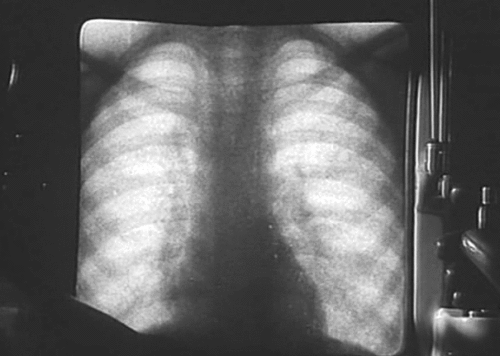

TDN > Actualité Le corps humain aux rayons X … en GIFs animés ! Publié par Elsa Fanjul le 11 Jan 2014 à 10:08 Suivez nous sur Google News Partagez cet article En bonus, découvrez le Giphoscope, ou comment faire des GIFs dans la vraie vie ! Veuillez laisser ce champ videRejoignez nos 875 726 abonnés en recevant notre newsletter gratuite N'oubliez pas de cliquer sur l'email de validation pour confirmer votre adresse email. Si vous ne l'avez pas recu vérifiez dans vos spams. Dernière étape pour confirmer votre inscription : il faut cliquer l'email de confirmation. Vérifiez dans vos spams si vous ne l'avez pas reçu ! A bientôt ! Page précédente Laissez un commentaire Votre adresse e-mail ne sera pas publiée. Les champs obligatoires sont indiqués avec * Votre commentaire * Votre pseudo * Votre adresse e-mail * Cliquez ici pour commenter